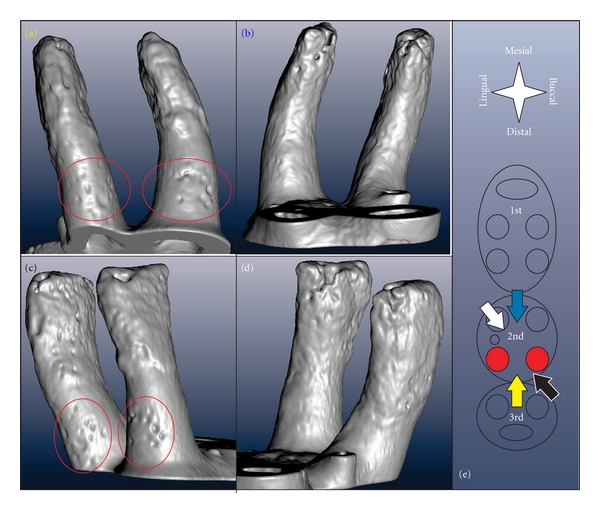

适应大鼠牙槽复合体是用各种成像方式说明。用于三维建模的微x射线计算机断层扫描,结合互补技术,包括图像处理、扫描电子显微镜、荧光标记、常规组织学(H&E、TRAP)和免疫组织化学(RANKL、OPN),阐明了大鼠牙周组织中骨、牙周韧带间隙和牙骨质的动态特性。断层扫描和电子显微镜以更高的分辨率显示钙化组织的结构适应。正在进行的生物矿化分析使用荧光标记,并通过评估衰减剖面从三维断层扫描的虚拟切片。通过结合组织学、免疫组织化学和断层扫描来说明破骨细胞分布作为解剖位置的功能。虽然断层扫描和扫描电镜提供了过去的吸收相关事件,但未来的适应性变化是通过免疫组织化学鉴定基质生物分子来推断的。因此,在大鼠牙槽嵴复合体的动态图片被说明。

Adaptation of a rat dentoalveolar complex was illustrated using various imaging modalities. Micro-X-ray computed tomography for 3D modeling, combined with complementary techniques, including image processing, scanning electron microscopy, fluorochrome labeling, conventional histology (H&E, TRAP), and immunohistochemistry (RANKL, OPN) elucidated the dynamic nature of bone, the periodontal ligament-space, and cementum in the rat periodontium. Tomography and electron microscopy illustrated structural adaptation of calcified tissues at a higher resolution. Ongoing biomineralization was analyzed using fluorochrome labeling, and by evaluating attenuation profiles using virtual sections from 3D tomographies. Osteoclastic distribution as a function of anatomical location was illustrated by combining histology, immunohistochemistry, and tomography. While tomography and SEM provided past resorption-related events, future adaptive changes were deduced by identifying matrix biomolecules using immunohistochemistry. Thus, a dynamic picture of the dentoalveolar complex in rats was illustrated.